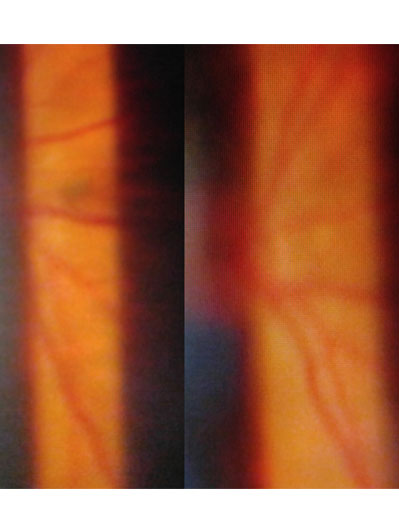

「飛蚊」是一種很常見的視覺障礙,一般是形容視覺上出現可跟隨眼睛移動而浮游的暗黑障礙物,形狀可呈點狀,線狀,網形,孤形或環形。嚴格來說,「飛蚊症」並不是一種眼疾,而是一種視覺上的不適症狀。成因大部份是由於眼內呈啫喱狀的玻璃體,出現液化,而形成各種形狀和大小不一的「殘留物」。「飛蚊症」其他成因亦可以是由於玻璃體出現出血或發炎等病變而導致。常見玻璃體出血的原因包括視網膜撕裂,視網膜脫落和糖尿上眼等等。所以如患深近視,糖尿病患者或出現突發性嚴重飛蚊症狀,應盡快求醫,作出詳細眼睛檢查。

年屆四十至五十歲的病人,出現急症飛蚊大多是由於玻璃體液化以至出現「後玻璃體脫落」,當玻璃體從視神經盤脫離時,往往便出現較大和明顯的玻璃體「殘留物」,而導致嚴重飛蚊症狀,小部份病人亦會出現視網膜裂痕,出血和脫落等併發症,以致危害視力。雖然大部份病人沒有視力嚴重受損的風險,但較嚴重的飛蚊症狀會帶來視覺上的不便。治療此類飛蚊症,一般藥物治療效果有限,而侵入性外科手術 (玻璃體切除) 亦只適合如玻璃體出現嚴重出血或撕裂等併發症患者。